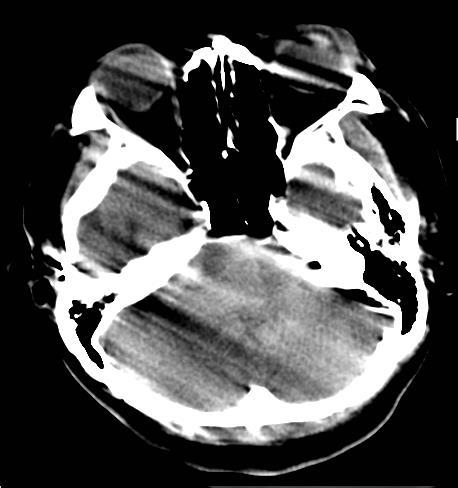

20% of annual MRI repeats, caused by motion artifacts (Andre JB et. al 2015)

Errors of up to 67% in measured SUV due to bulk motion in PET images (Kolbitsch, et. al 2014)

Severe head motion reported in 25% of CT brain perfusion scans for stroke patients.(Fahimi et. al 2013)

L’IRM, technique d’imagerie médicale non invasive, est très sensible aux mouvements du patient car l’acquisition spatiale se fait de manière ségmentée. L’information complète requiert une séquence longue. En effet, l’IRM ne fait pas directement une image comme en rayon-X (RX ou CT-scan). En IRM, Le signal de résonance magnétique mesuré est enregistrée dans l’espace des fréquences spatiales appelé “espace-K”. L’image finale utilisée par les radiologue est obtenue par “reconstruction” via une transformation mathématique, la transformée de Fourier.